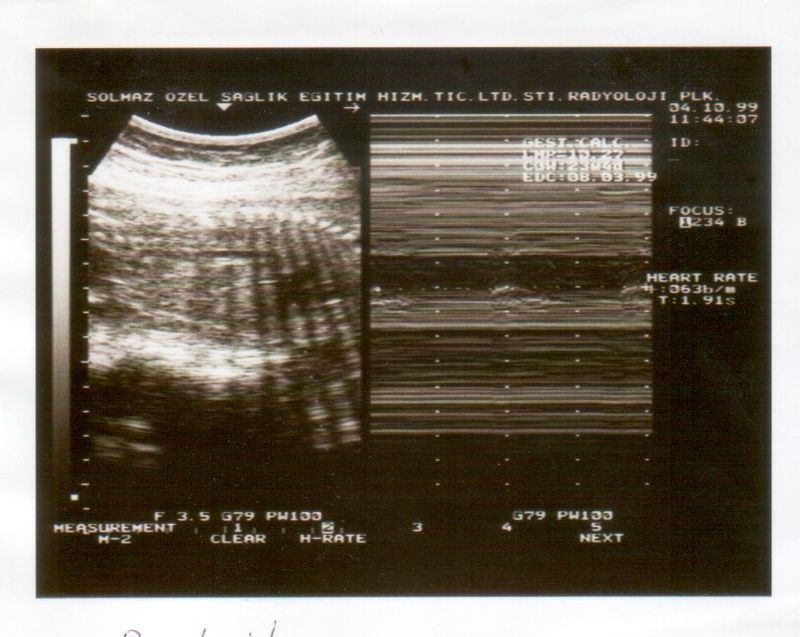

Biophysical Profile Scoring (BPS) is a comprehensive prenatal test that evaluates the well-being of the fetus using ultrasound and non-stress tests. This scoring system assesses five critical components fetal heart rate, fetal breathing movements, fetal movements, fetal muscle tone, and amniotic fluid volume. By providing a detailed overview of the baby's health, BPS offers expectant mothers the peace of mind they desperately seek.

Sunita’s biophysical profile score was conducted at Navodaya Sonography, a trusted clinic known for its advanced prenatal care services. The results of the test were reassuring. The detailed report showed that her baby was developing normally, with no signs of distress or complications. The clear and comprehensive information provided by the BPS alleviated Sunita’s worries.